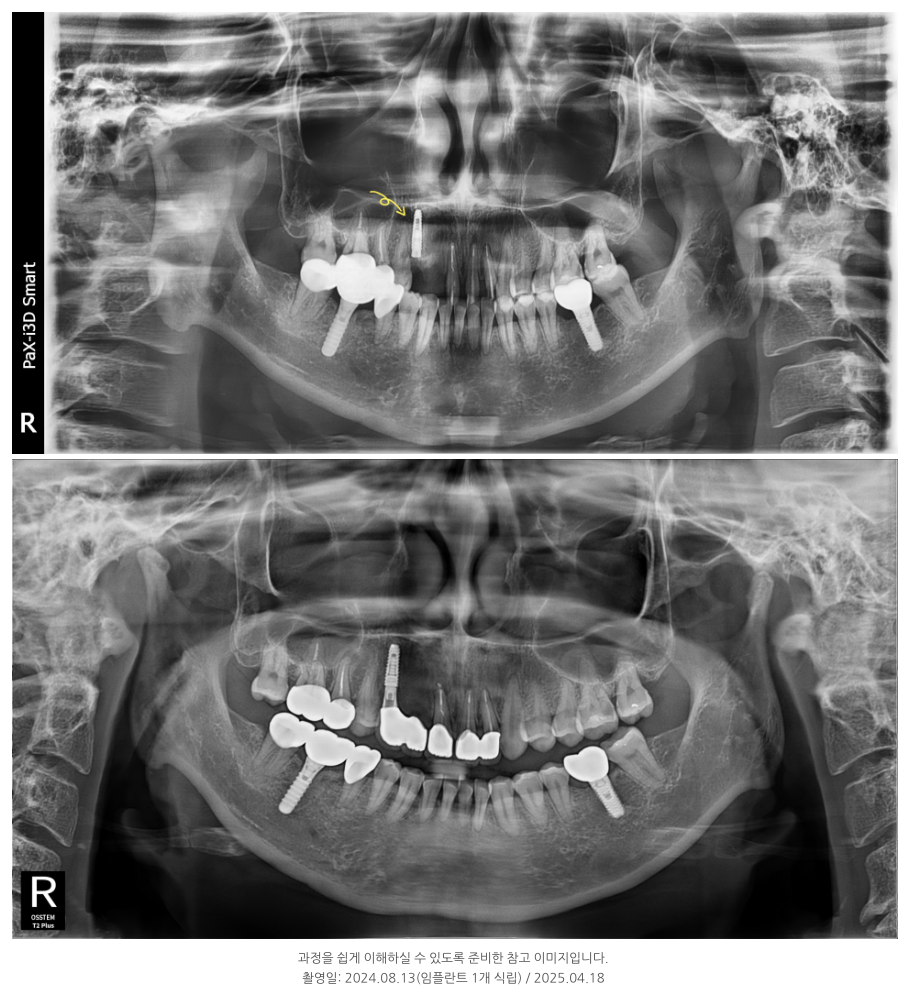

얼마 전 50대 여성 환자분이 내원하셨습니다.

오래 전에 앞니 신경치료를 하고 5개 보철물을 연결해 사용하시던 분이었는데,

이 환자분 역시 뿌리 끝 염증과 충치가 발견되어, 현미경을 통한 재신경치료가 먼저 필요했습니다.

또, 일부 치아는 손상이 심해 발치 후 임플란트를 진행했습니다.

이번 환자분은 이전처럼 5개를 하나로 묶지 않고,

2-1-2 구조로 나누어 보철을 진행했습니다.